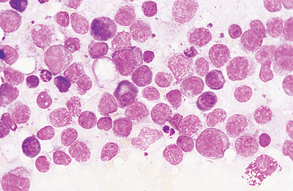

In a normal lymph node, the predominant cell type is the small, mature lymphocyte. These tend to comprise more than three fourths of the total cells present. Smaller numbers of intermediate lymphocytes and lymphoblasts as well as macrophages are also present. Plasma cells may occasionally be seen (Fig. 9-44). Mast cells are usually rare in cytologic preparations of lymph node tissue. Lymph nodes with evidence of inflammation (lymphadenitis) will have a predominance of leukocytes, as previously described (Fig. 9-45).

Figure 9-44 Aspirate from a normal lymph node. Small, mature lymphocytes predominate. (From Raskin RE, Meyer DJ: Atlas of canine and feline cytology, St Louis, 2001, Saunders.)

Figure 9-45 Pyogranulomatous lymphadenitis. Numerous macrophages and neutrophils are evident along with a mixture of lymphocyte types. (From Raskin RE, Meyer DJ: Atlas of canine and feline cytology, St Louis, 2001, Saunders.)

Lymph nodes that are responding to antigenic stimulation also contain predominantly small, mature lymphocytes. However, plasma cells, lymphoblasts, and intermediate lymphocytes are more abundant than in a normal lymph node (Fig. 9-46). Occasional Mott cells (plasma cells containing secretory vesicles of immunoglobulin) may also be seen (Fig. 9-47). Antigenic stimulation can also cause an inflammatory response and would be characterized by the presence of neutrophils and/or macrophages.

Primary lymphoid neoplasia, or lymphoma, is characterized by a predominance of lymphoblasts, and mitotic figures are common. Macrophages are also present, and plasma cells are scarce. Other neoplastic cells that may be present in lymph node aspirates include mast cells, carcinoma cells, sarcoma cells, and histiocytes. Cells that display at least three abnormal nuclear configurations usually are identified as malignant (Fig. 9-48). Lymph node samples may also contain metastatic cells from other body parts (Fig. 9-49).